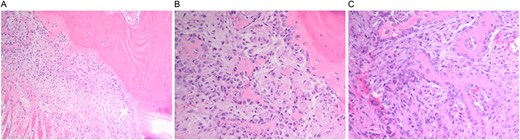

A multidisciplinary discussion involving orthopedic, maternal-fetal medicine, and head and neck teams determined the treatment plan. Further biopsy confirmed the brown tumor diagnosis, showing multinucleated giant cells, mononuclear stromal cells, bone resorption, and osteoclast clustering (Fig. 2A–C). Six days after the presentation, she was deemed suitable for parathyroidectomy. Although at high risk for pathologic fracture, she declined prophylactic fixation during pregnancy. Two days after a successful parathyroidectomy, she underwent an uncomplicated Cesarean section. As her calcium levels normalized, plans for femoral fixation were made post-childbirth. One week postpartum, the patient fell, resulting in a pathologic fracture of the left distal femur and ipsilateral iliac wing fracture (Fig. 3A and B).

(A–C). Histopathologic images from biopsy specimen at 100× and 200× magnification, showing numerous multinucleated giant cells and mononuclear stromal cells with marked resorption of bone trabeculae and clustering of osteoclasts.